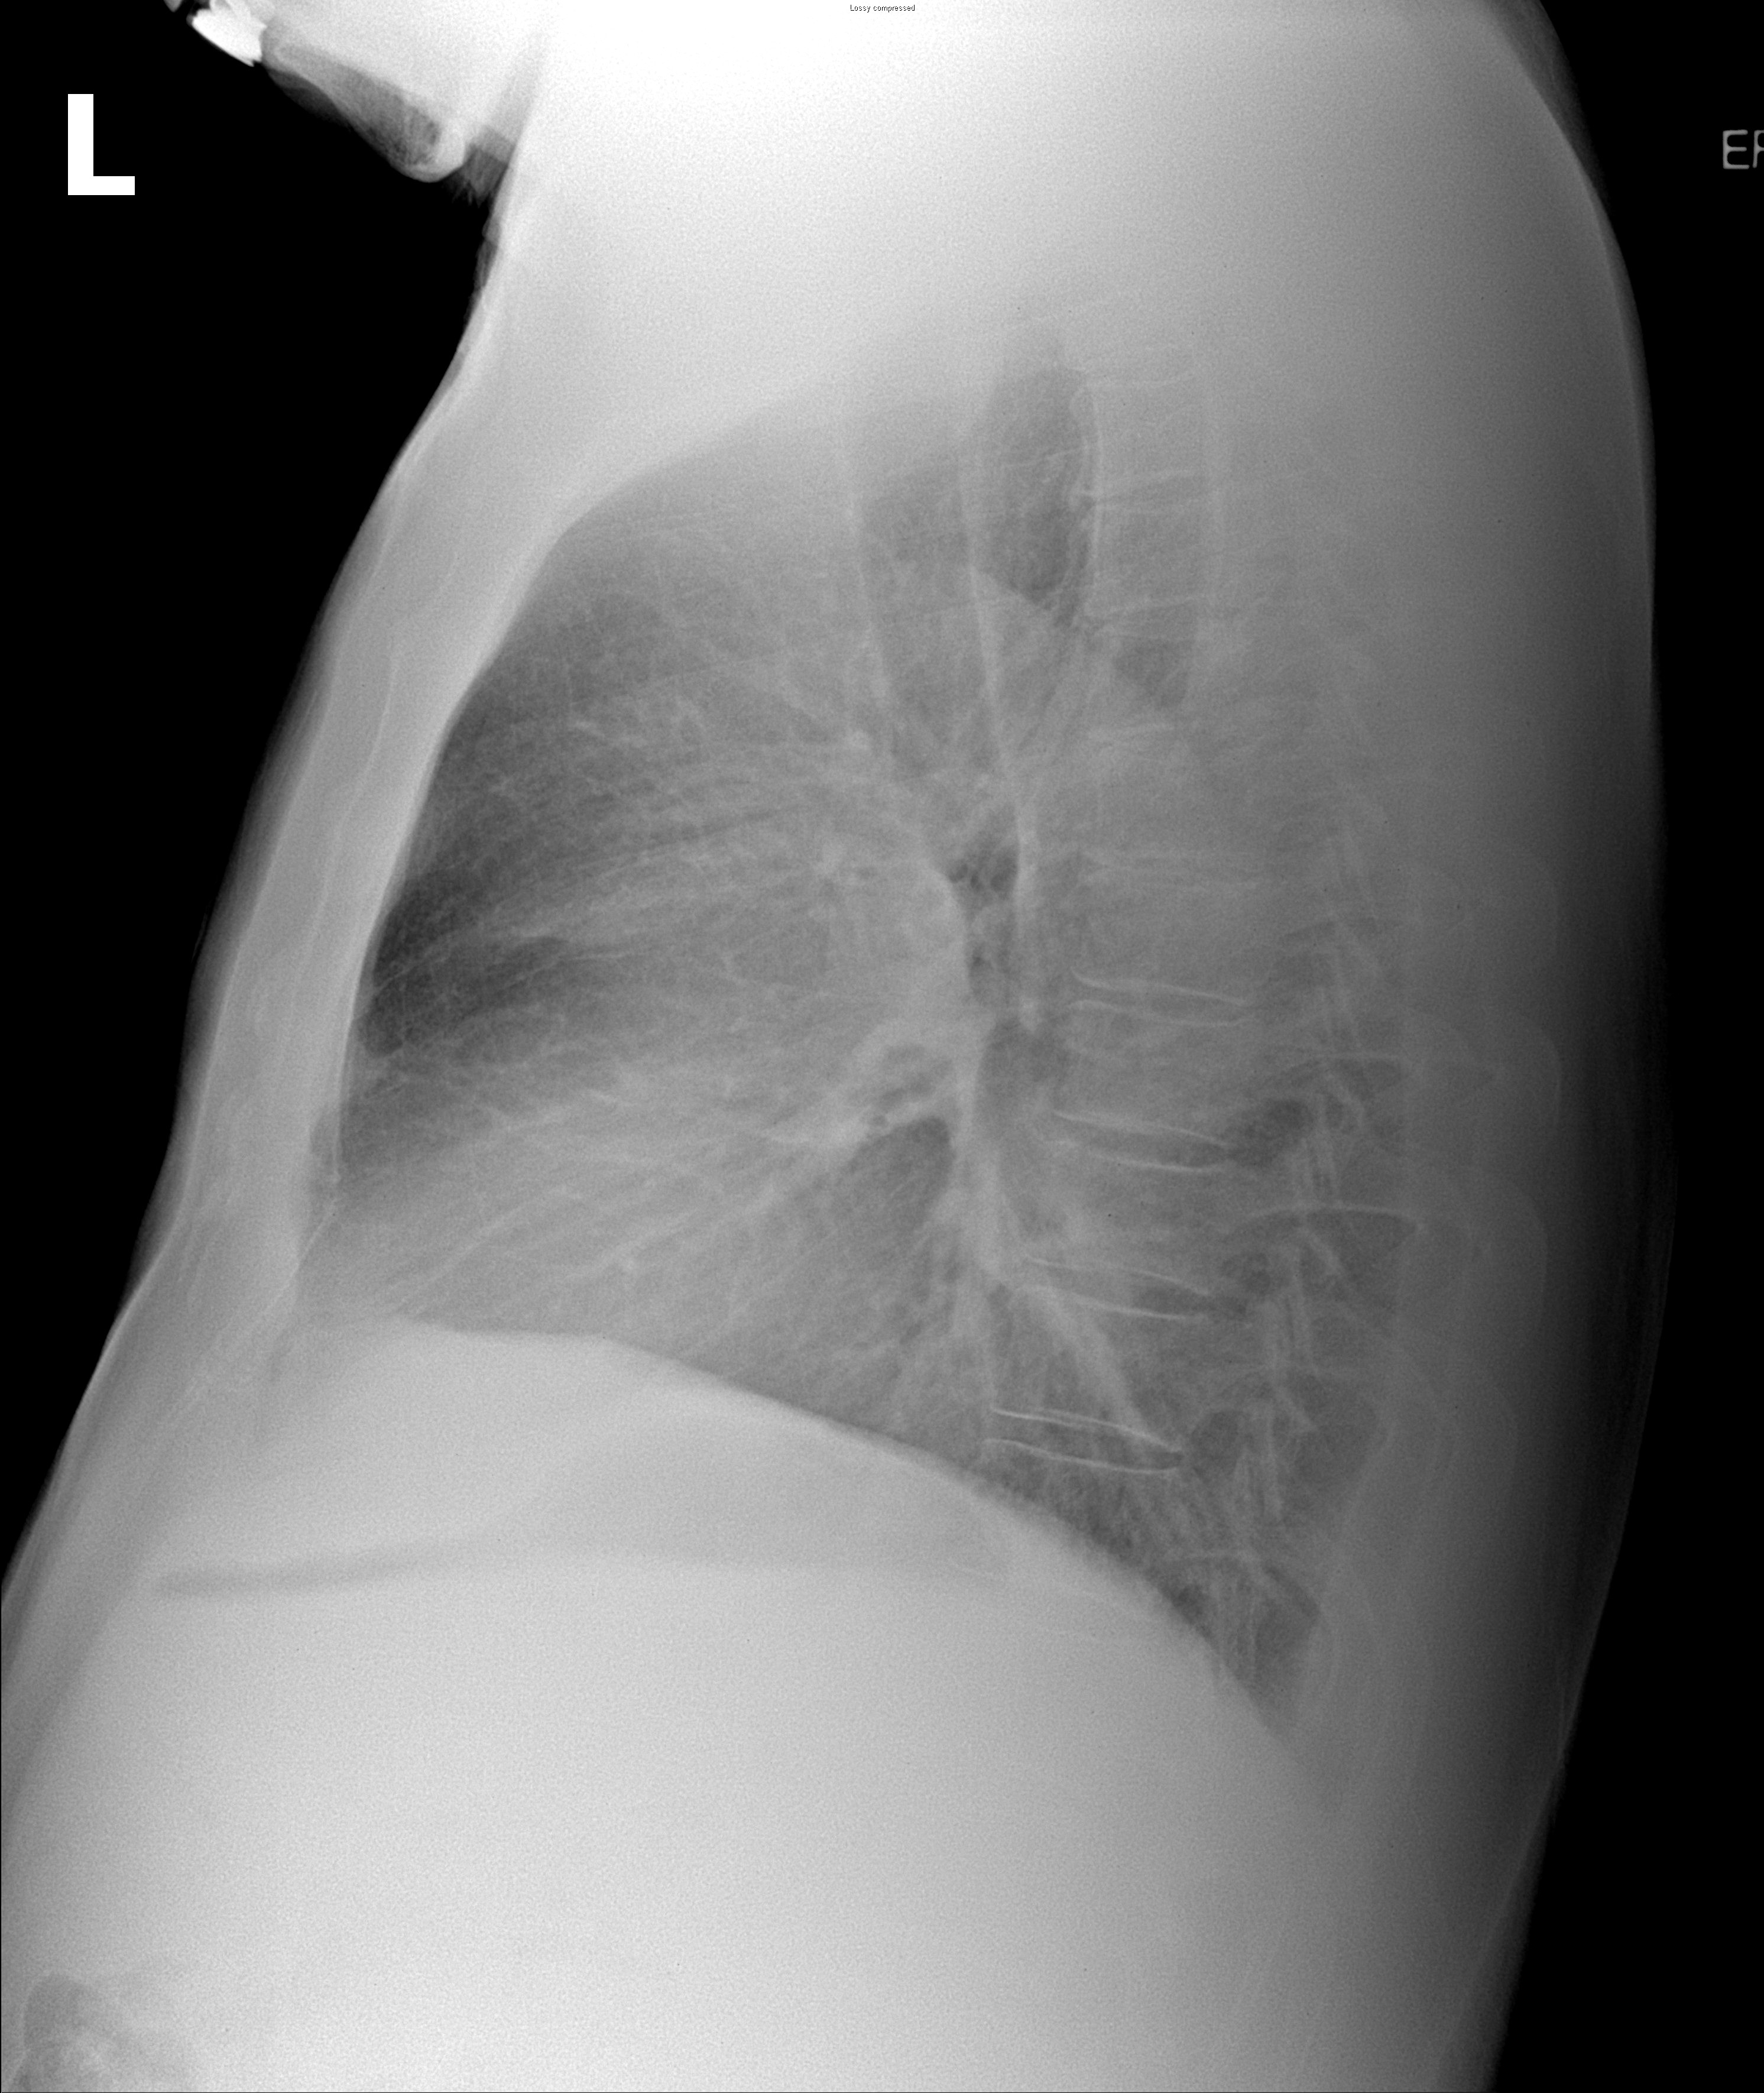

69¼¼ ³²È¯ DM,HTN °ú°Å·Â ÀÖ´ø ȯÀÚ·Î ³»¿ø 10³âÀüºÎÅÍÀÇ right pleural chest pain À» ÁÖ¼Ò·Î ³»¿øÇÑ È¯ÀÚÀÇ CxR ¹× Chest CTÀÔ´Ï´Ù.